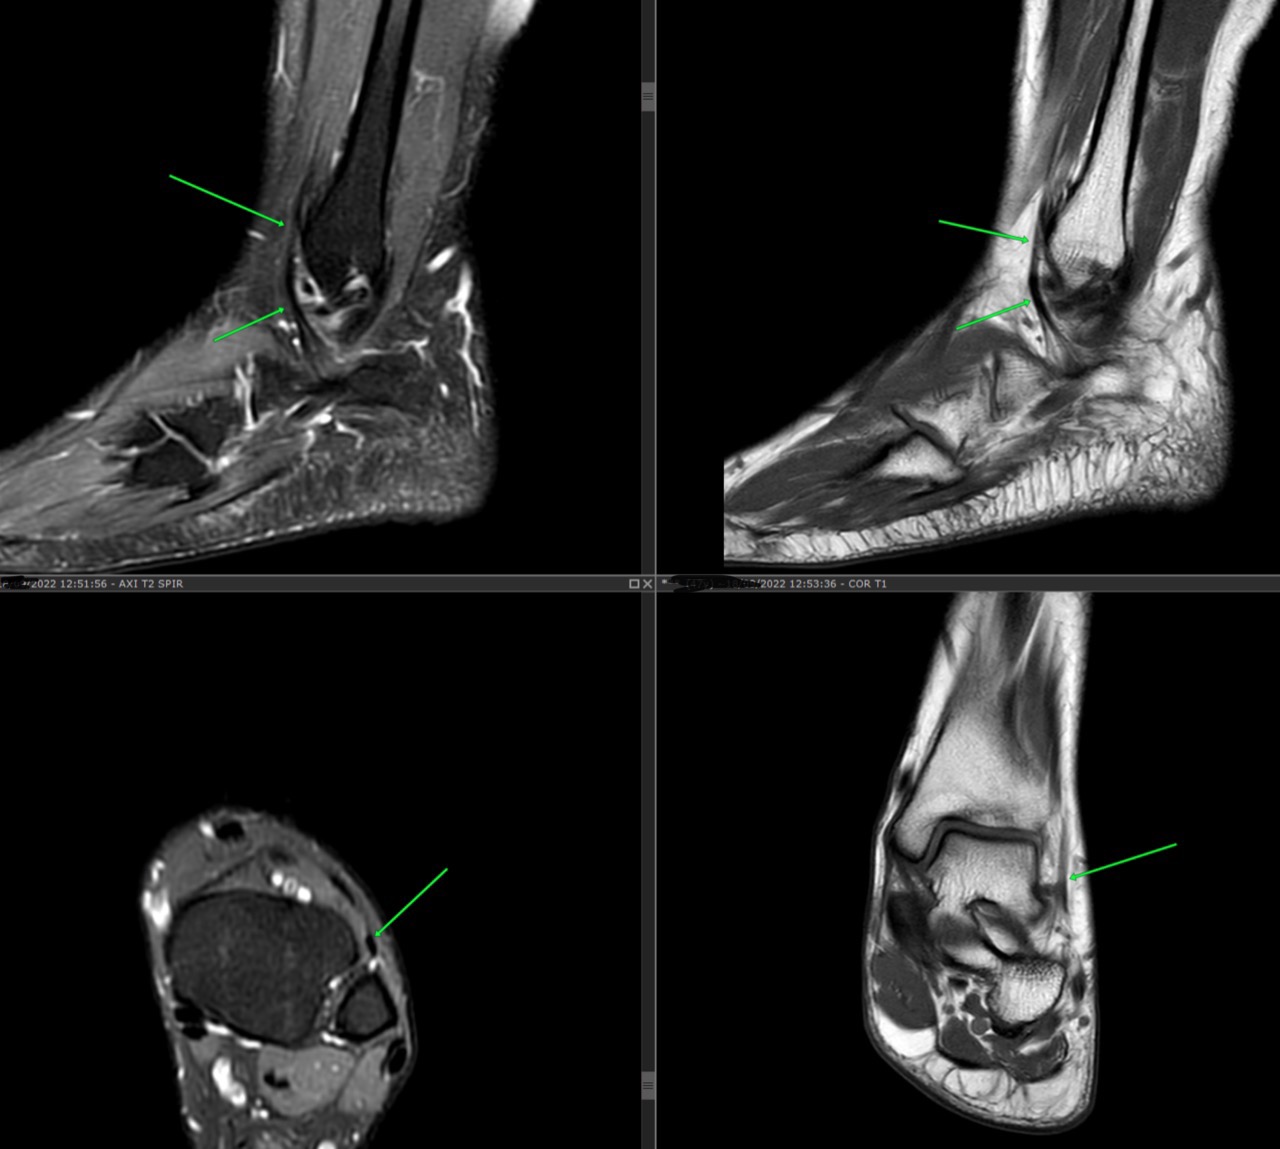

– Anterior fibulocalcaneus muscle: accessory muscle within the anterior compartment

“ These muscles originated from the fibula, anterior crural septum, and the investing fascia of the fibularis tertius, and they passed anterior to the lateral malleolus and inserted on the calcaneus, anterosuperior to the fibular trochlea. ”

From the paper: An anterior fibulocalcaneus muscle: An anomalous muscle discovered in the anterior compartment of the leg doi.org/10.1002/ca.21074